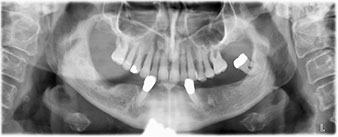

A three-dimensional cone beam computed tomography scan (CBCT, Planmeca) was performed to aid planning and minimize risks. This revealed that the quality and quantity of the available bone were sufficient for the surgery and immediate restoration using the Fast & Fixed method. Following the protocol for this concept, the implants are inserted at 35, 32, 42 and 45. Angling the distal implants by up to 45° shifts the emergence profile to posterior and generates a larger support polygon (Fig. 3).

Fast & Fixed method

Fig. 3